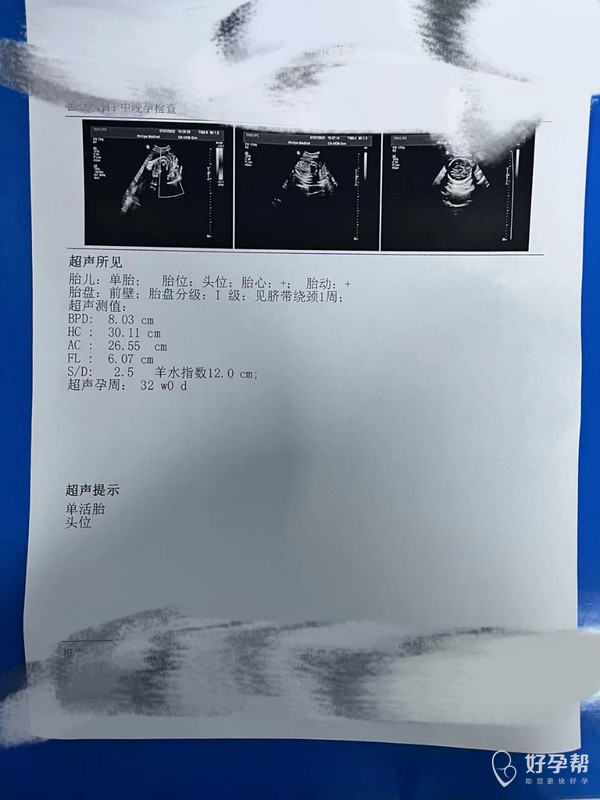

大夫你好31加6周上一胎孩子腿不长这个腿可以

你好,孩子大小可以,腿不短,有一圈脐带绕颈,注意好胎动,快32周了,2周产检一次,36周后每周产检一次,祝好孕。